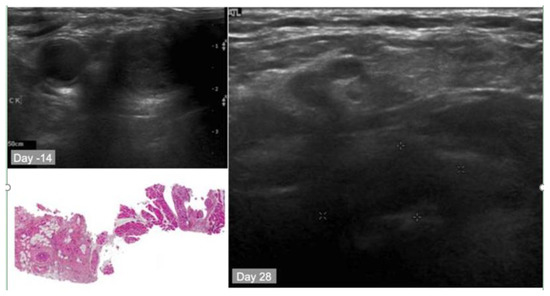

10.2. Case Study

- Sultan, A.A.; Jerjes, W.; Berg, K.; Hogset, A.; Mosse, C.A.; Hamoudi, R.; Hamdoon, Z.; Simeon, C.; Carnell, D.; Forster, M.; et al. Disulfonated tetraphenyl chlorin (TPCS2a)-induced photochemical internalisation of bleomycin in patients with solid malignancies: A phase 1, dose-escalation, first-in-man trial. Lancet Oncol. 2016, 17, 1217–1229. [Google Scholar] [CrossRef]